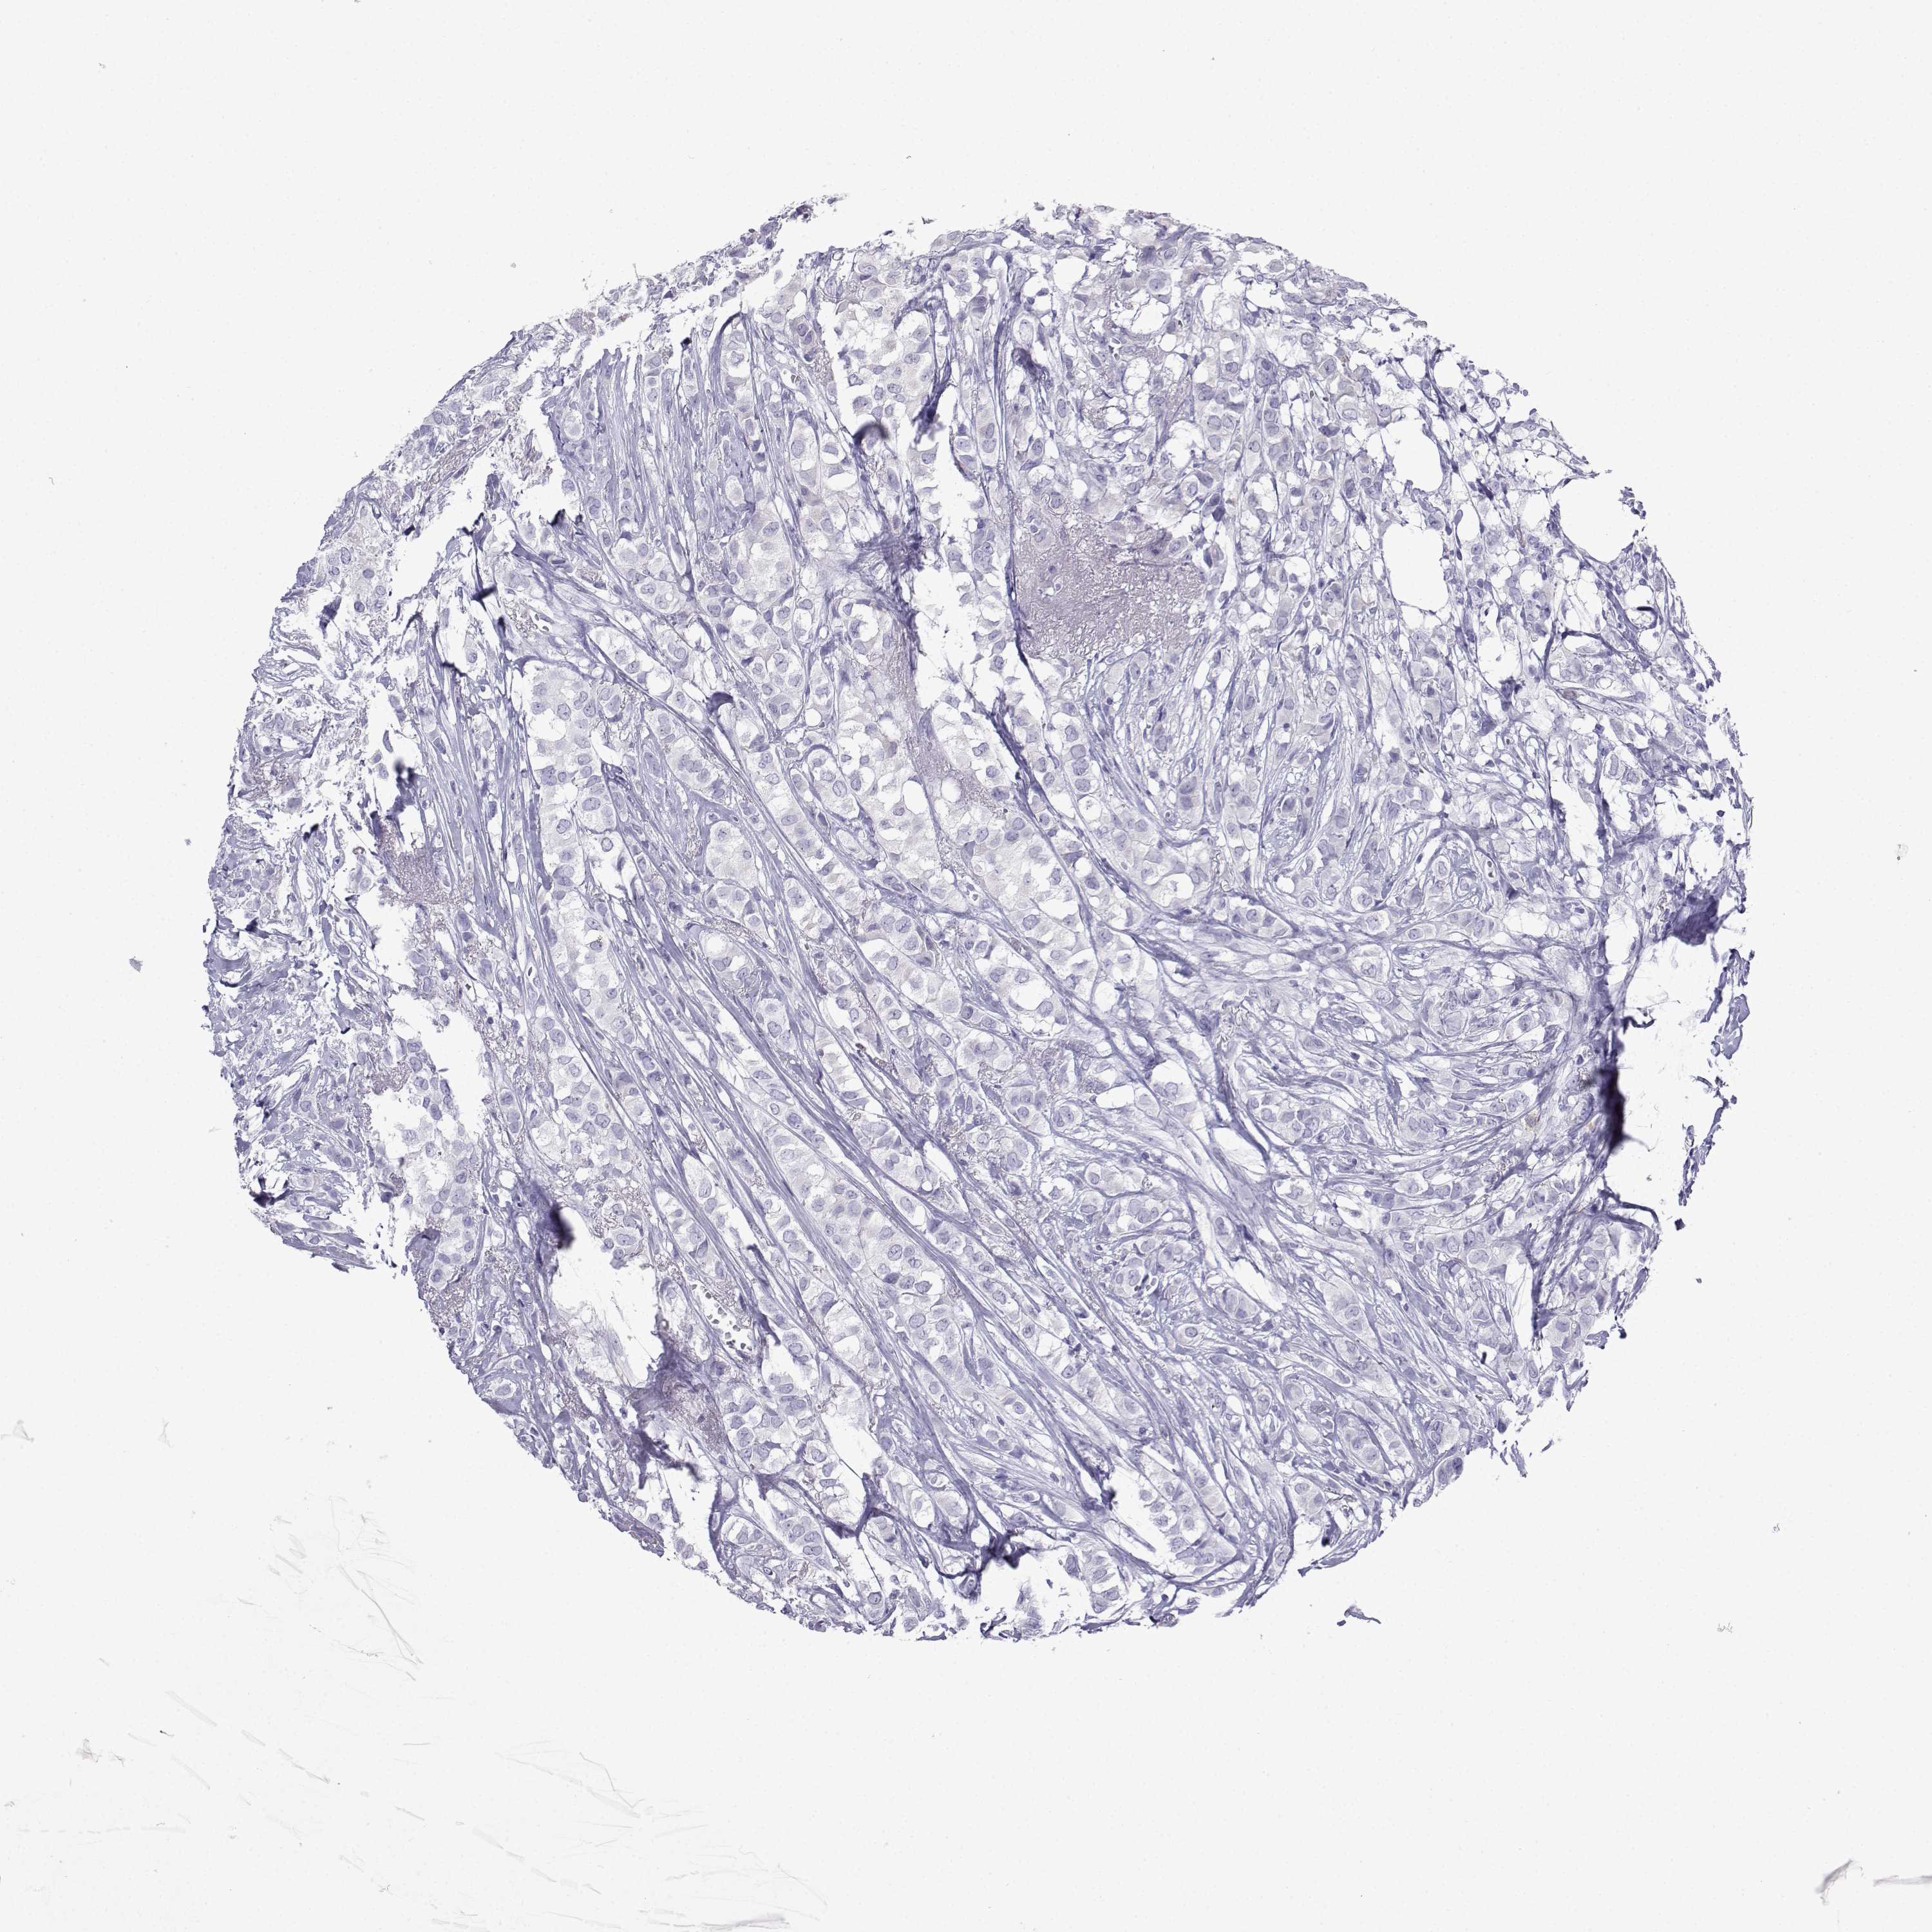

BRCA TCGA BRCA VALIDATION PROTEIN EXPRESSION

Breast cancer

Human cancer